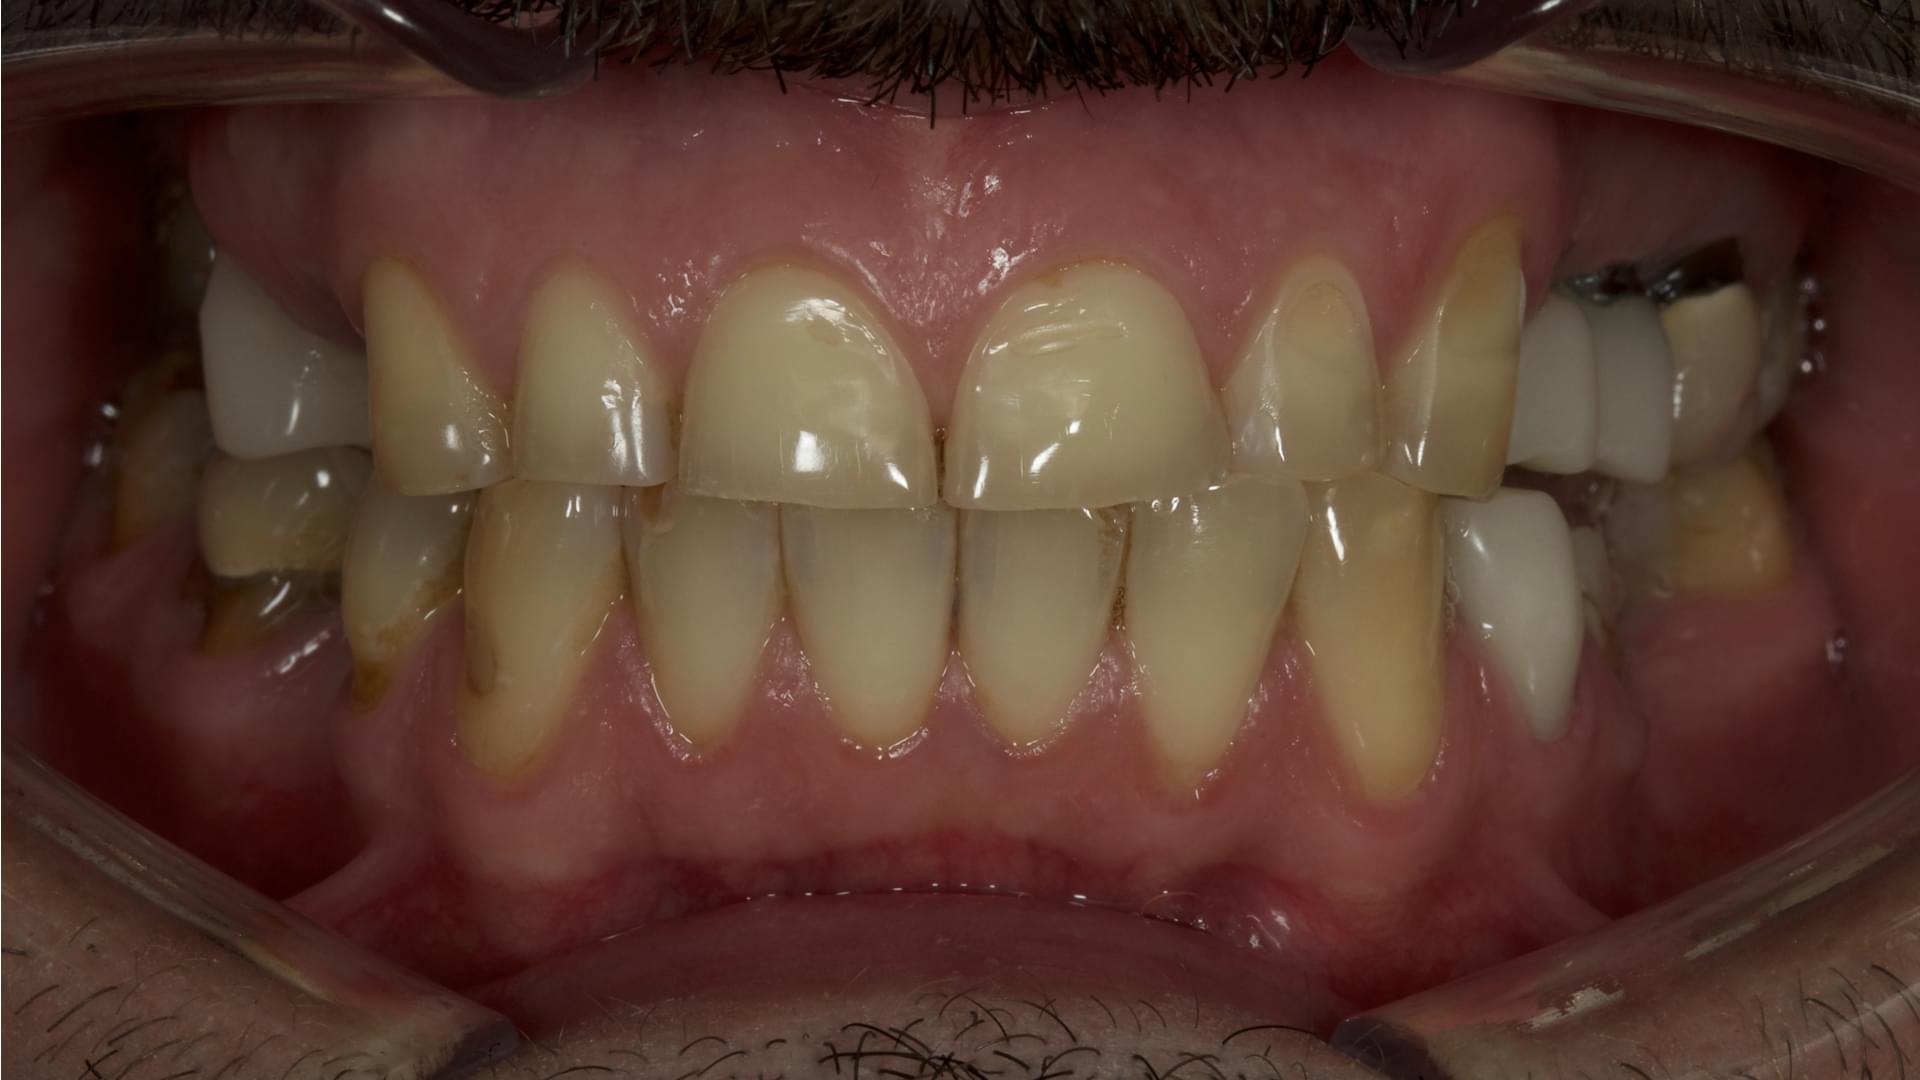

Acoperirea dinților cu punți și coroane metalo-ceramice, odată cu trecerea timpului, afectează gingiile și rădăcinile. Atunci când are loc îndepărtarea gingiilor de punțile metalo-ceramice, se descoperă un profil metalic negru și inestetic. De asemenea, are loc acumularea alimentelor și carierea rădăcinilor care susțin capsulele. Acum este posibilă înlocuirea coroanelor și punților cu implanturi dentare, astfel obținând un zâmbet natural și estetic.

Implanturi Dentare 🔥 Cazuri finisate #1